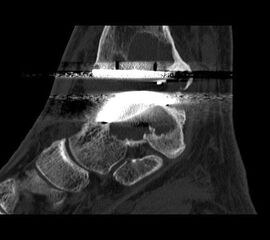

• Optional CT; insbesondere bei ausgedehnten Knochendestruktionen.

• Prothesenplanung anhand von Röntgenschablonen (Abb. 1 und 2).